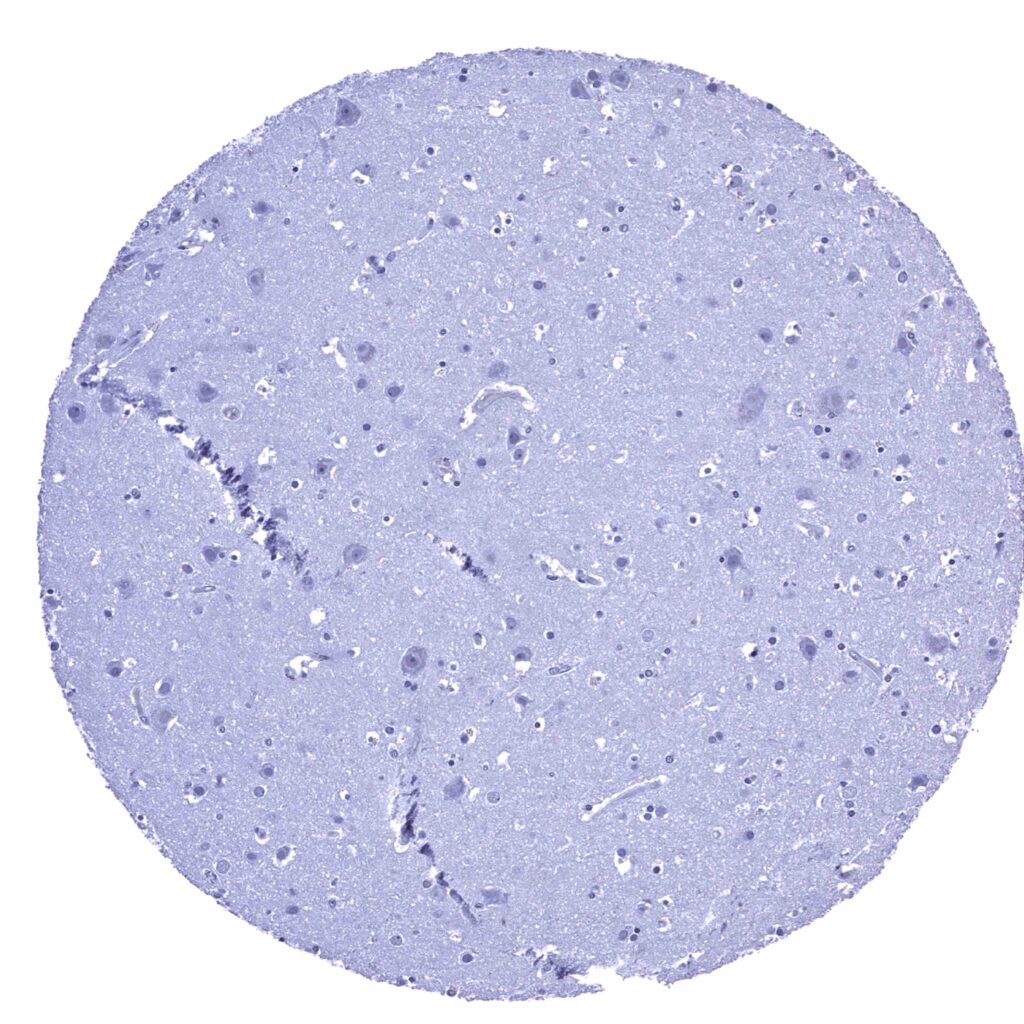

Cerebrum, grey matter